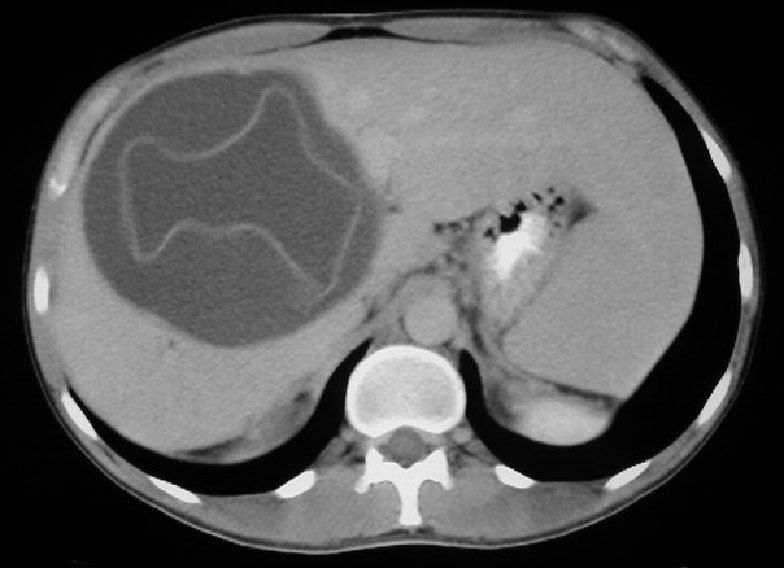

SIGNO DE LA VESÍCULA HIJA

En el quiste hidatídico hepático y otros órganos abdominales, la presencia de vesículas hijas (quistes dentro del quiste) puede verse tanto en la ecografía como en el TC (flechas blancas) y en resonancia magnética. Además del quiste del lóbulo hepático izquierdo, que muestra el signo, hay otro quiste hidatídico con pared calcificada en el lóbulo hepático derecho (flecha roja).

Más información en: von Sinner, WN. New diagnostic signs in hydatid disease: radiography, ultrasound, CT and MRI correlated to pathology. European Journal of Radiology 1991; 12:150-159.